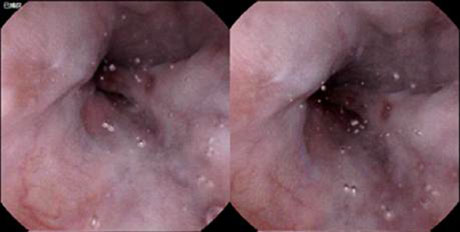

7、 回末淋巴滤泡增生

69岁,男性,年度体检,畏惧胃肠镜,胶囊内镜示回末淋巴滤泡增生。